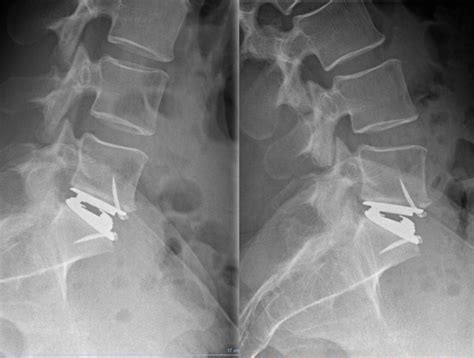

Total Disc Arthroplasty Offers A New Life For Spine Patients

How Long Does a Cervical Disc Arthroplasty Recovery Take?